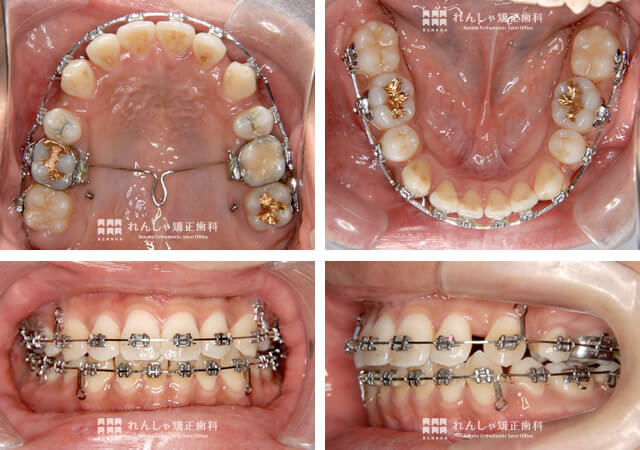

治療開始から約2年。S.Tさんの歯列のスペースは、ほぼ閉鎖しました。

上奥歯は歯科矯正用アンカースクリューで引っ張られ、上前歯も自動的に後方へ移動しますが、下前歯が前突したままでは上前歯を後退させることはできません。そのため、ご自身で上奥歯から下前歯に矯正用エラスティック(ゴム)を装着してもらうことにしました。

治療が終了しました。

当初目標にしていたがたつきの改善と口元の後退は達成できましたが、実はこのあと少し問題がありました。